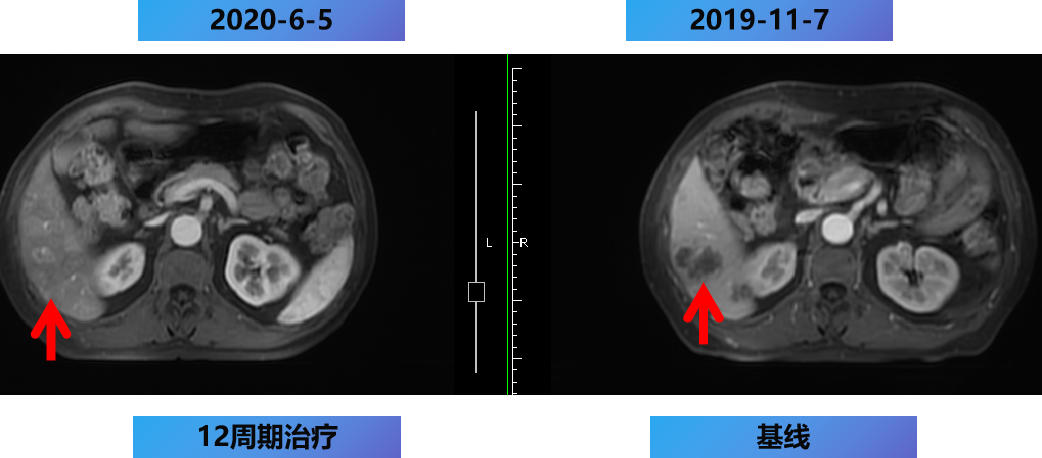

【治疗方案疗效评估】

MDT意见:肝转移灶可切除,肺转移灶缩小。

治疗目标:NED。

治疗策略:原发灶切除和肝转移灶切除,肺转移灶择期手术。

12周期化疗+手术+肝转移灶切除及消融。

2020-7-5 复查腹部MRI示:乙状结肠癌伴肝转移治疗后改变,对比2020-6-18 MRI,肝内治疗灶凝固坏死显著,肝内未见明显癌灶征象,部分周边反应性改变可能,建议3个月后随诊复查。